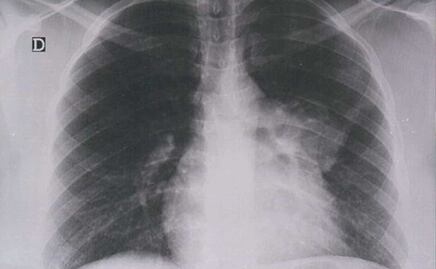

De acuerdo con los cálculos de organismos internacionales, el cáncer de mama, próstata, cervicouteriuno, colorrectal y pulmón son los más recurrentes en la población de ambos sexos.

-Pulmón, con una incidencia de 6.5 por cada 100 mil hombres.